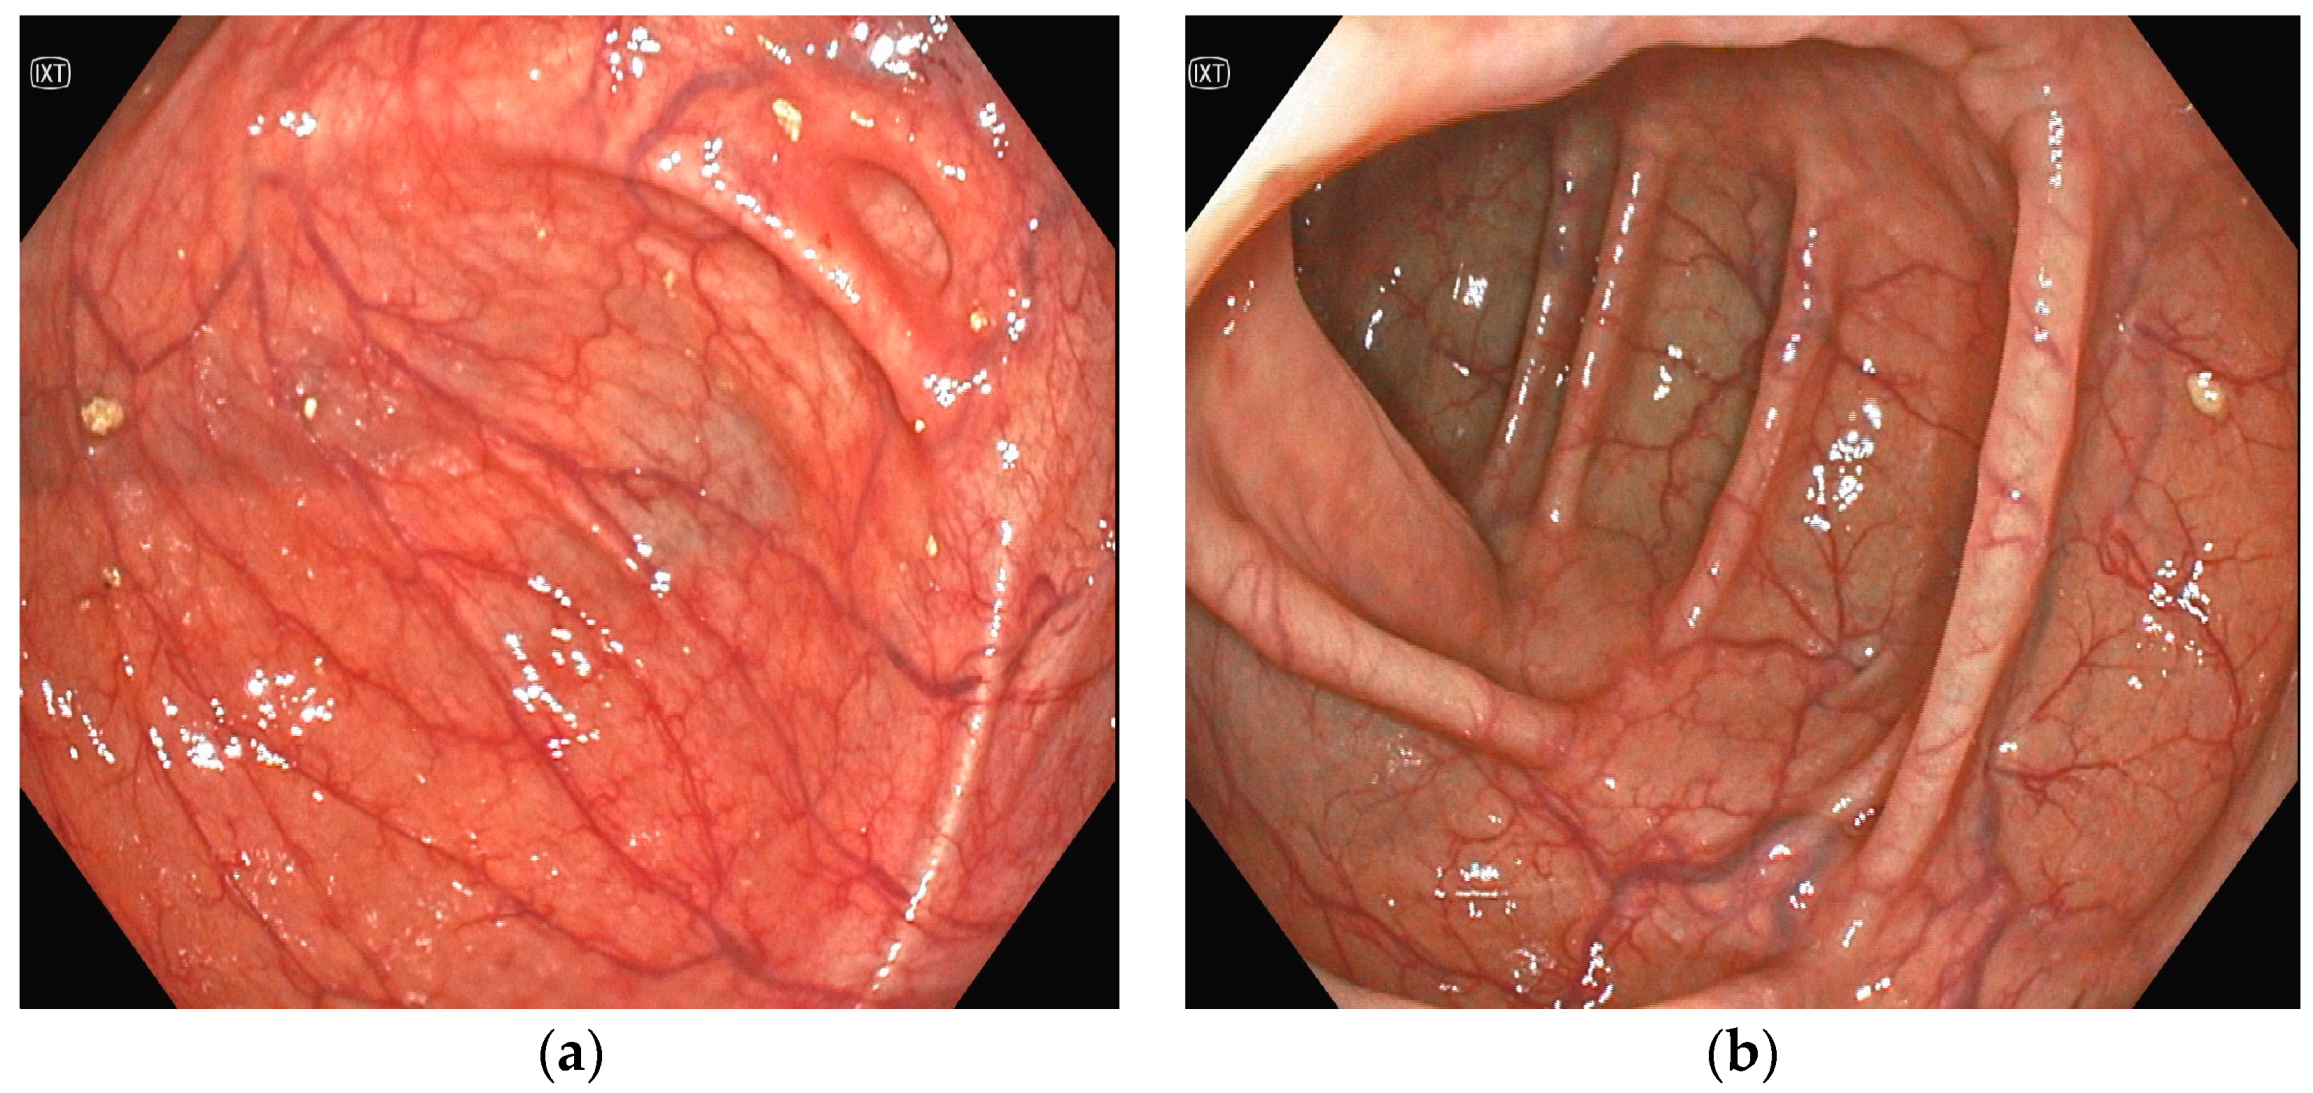

2. Case Presentation